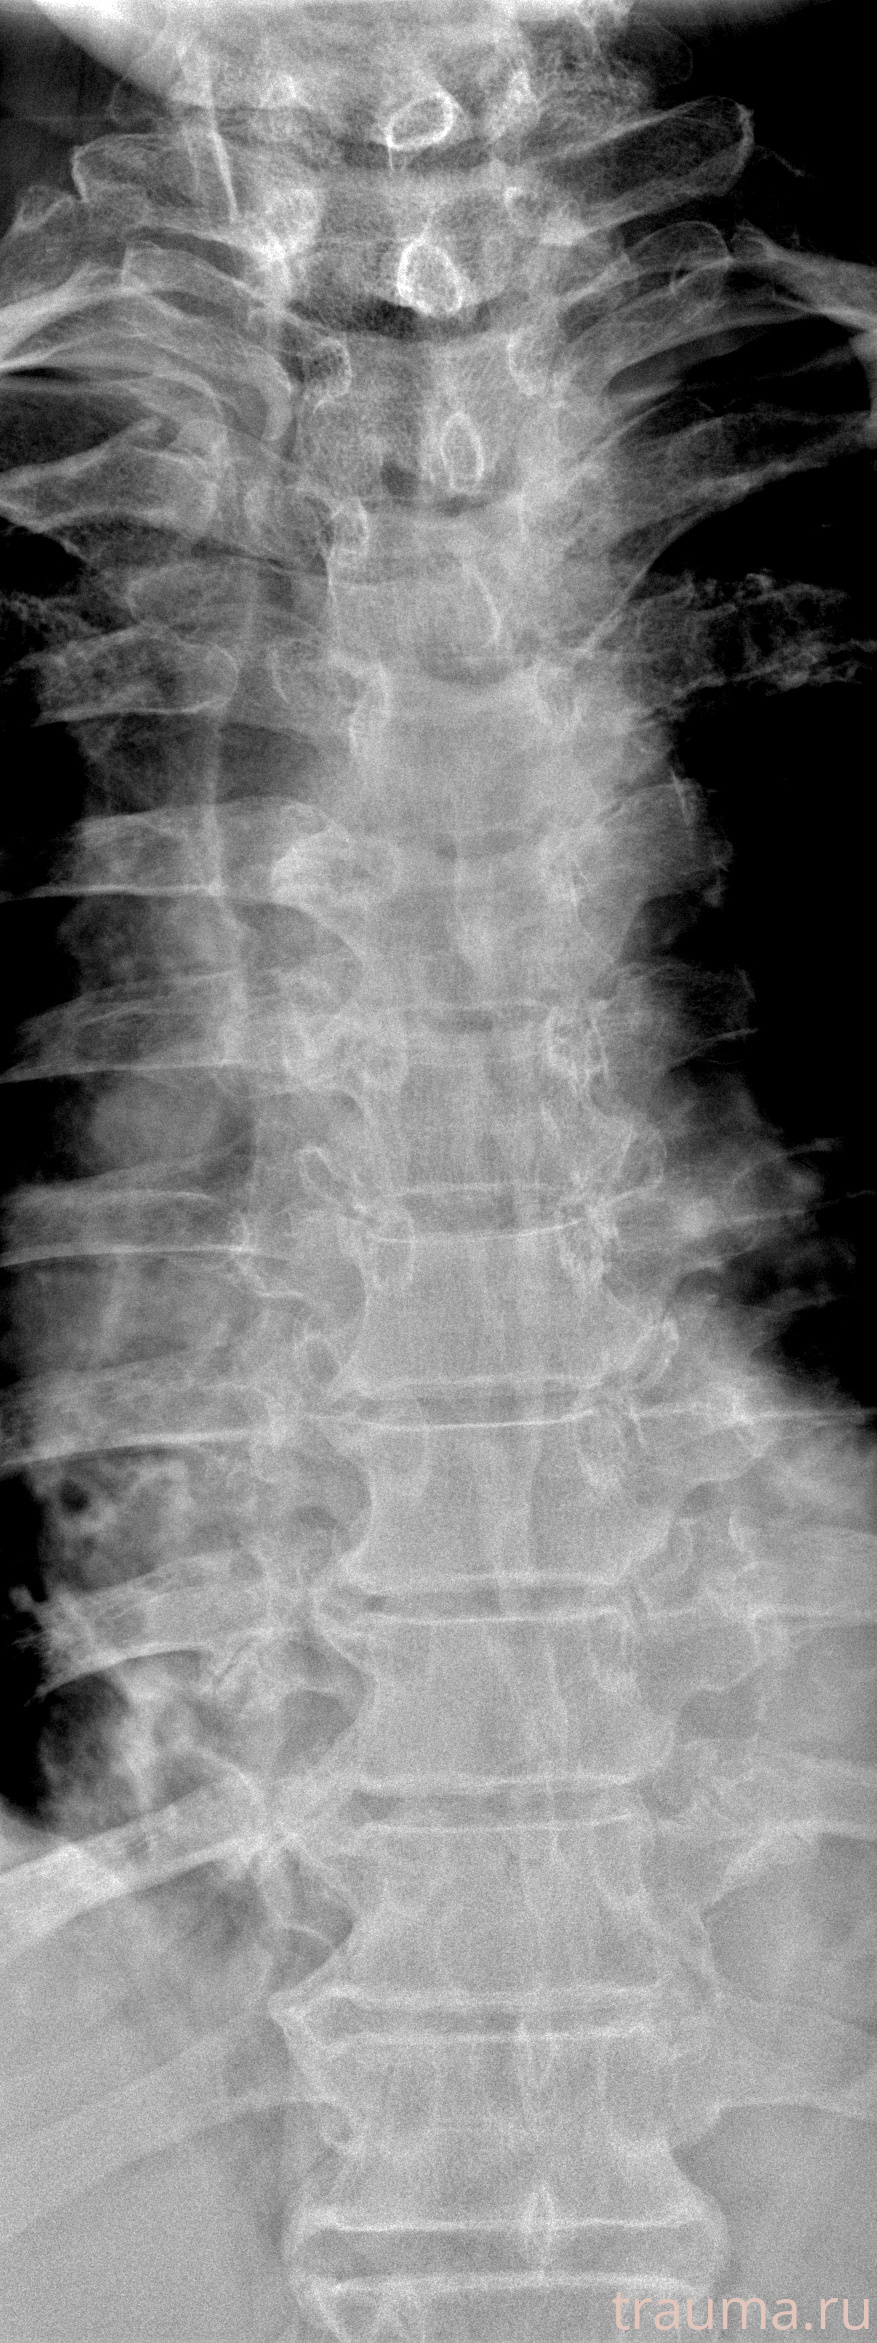

Рентген на дому: по вашему адресу приезжает врач-рентгенолог, травматолог-ортопед с мобильным рентгеновским аппаратом, проводит диагностику травмы или заболевания, делает необходимые рентгенограммы, дает рекомендации по дальнейшему лечению. Получить качественные снимки в домашних условиях возможно благодаря уникальной методике, разработанной МосРентген Центром для института  Склифосовского